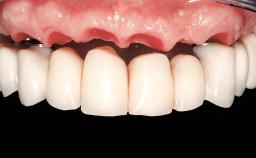

A 61-year-old male patient with a failing fixed maxillary rehabilitation and a fixed mandibular rehabilitation requested a new fixed maxillary rehabilitation. The patient was wearing a temporary metal-reinforced maxillary bridge inserted two years before the consultation. He reported that his previous dentist did not want to insert a definitive framework because he considered the residual teeth to have a negative prognosis. The patient reported a history of recurrent caries and endodontic complications as the main reason for the previous extractions. The anamnesis was negative for periodontal disease and bruxism. The patient’s chief compliant was the mobility of his maxillary prosthesis, which needed to be re-cemented frequently, and discomfort during chewing.Moreover, the patient was not satisfied with the esthetic appearance of his maxillary teeth, which he found too long. The patient asked for a stable and comfortable fixed maxillary rehabilitation and firmly rejected any removable solution.